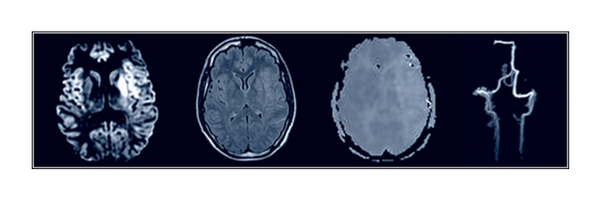

VISTA was established in 2001 with the aim of collating and providing access to anonymised clinical trial data for novel exploratory analyses.